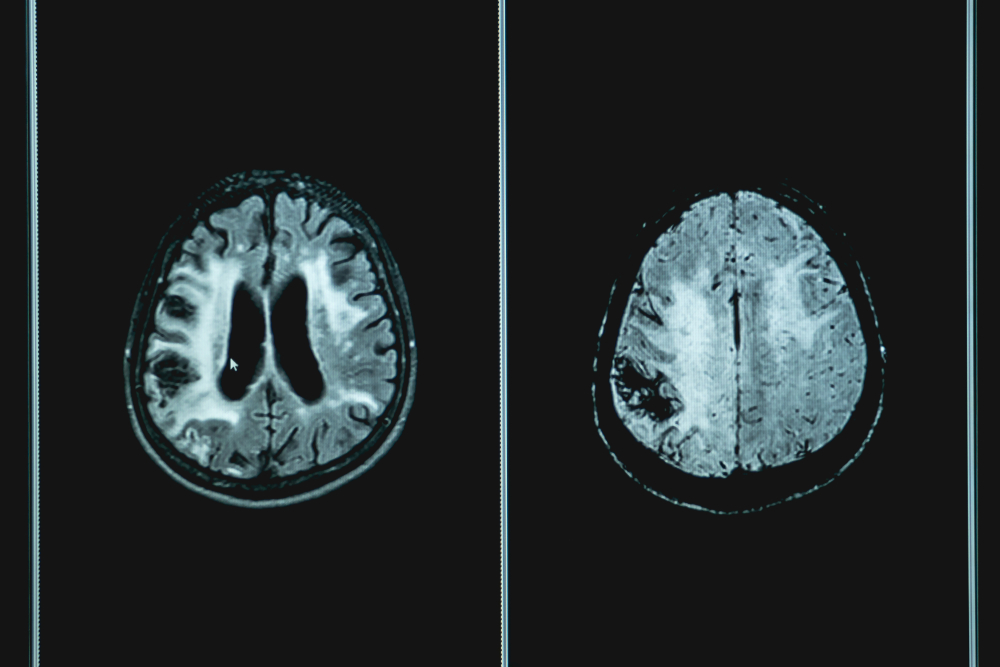

What is a Brain Hemorrhage

A brain hemorrhage is also referred to as a brain bleed or intracranial hemorrhage. According to Fairview.org, this occurs “in any part of the brain or between the brain and the skull.” Internal bleeding can cause damage to brain tissue, or in other words, “brain damage”. In severe cases such as Rai-Lèyah’s the damage is irreversible and often results in death. Estimates show that up to 1 in 5 children can suffer from this ailment with no apparent cause.

Testing for a brain hemorrhage can be conducted in several ways. The most well-known are blood tests or a CT/MRI. Other possible testing may include Angiography and transcranial Doppler testing. These scans take pictures of blood vessels in the brain. In less severe cases treatment options include observation and medication.